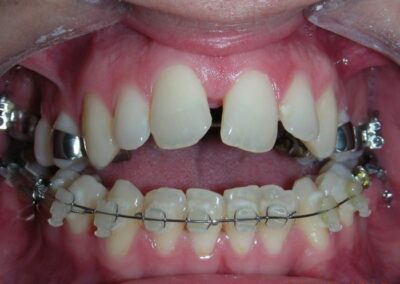

Intraoral Examination:

Absent #16, #36 and #46 , No Angle molar relationship . Projection of canines axes in class II relationship . Anterior open bite: Over Bite – 8 mm). Bilateral posterior crossbite: Involvement of upper posterior sectors with inverted buccal-lingual relationship. Moderate Crowding at the level of the upper and lower incisors. Acceptable Oral Hygiene with no periodontal issues

The patient presented with an anterior open bite, characterized by the absence of vertical overlap between the upper and lower incisors, and bilateral posterior crossbite. Extraoral examination revealed a vertically long facial pattern with an increased lower third of the face. The profile is convex with a retruded chin, indicating sagittal and vertical skeletal imbalances. We find also the inclined bipupillary line, which corresponds to facial asymmetries and altered occlusal plane.